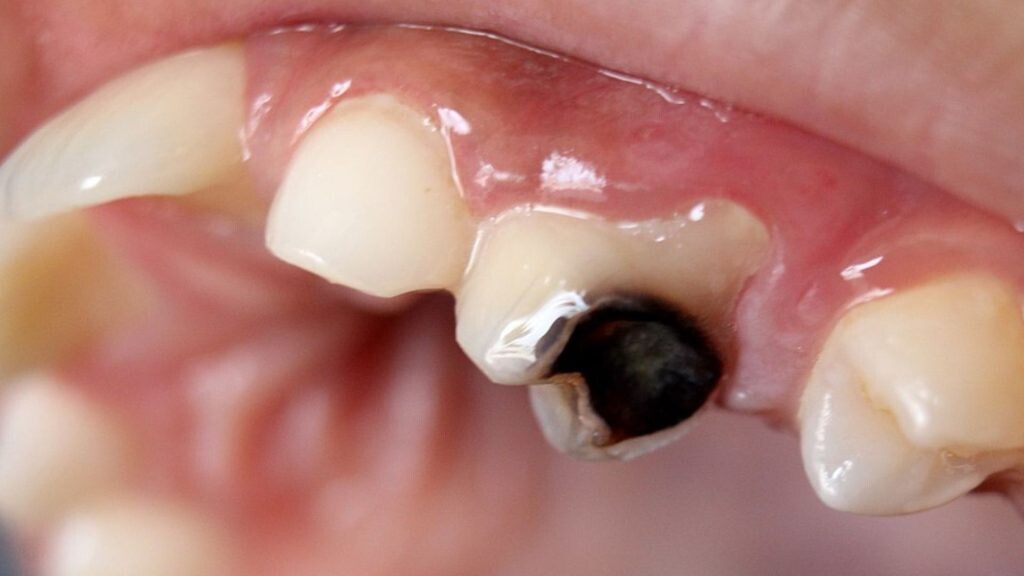

What Causes Tooth Decay

Bacteria from sugary foods and drinks, poor oral hygiene, and acidic drinks and foods are all factors that contribute to the development of tooth decay. When left untreated, this can lead to an infected pulp, which requires root canal treatment to remove the infected pulp chamber and replace it with a temporary filling. Endodontic treatment is successful in over 95 percent of root canals, however, regular checkups are essential to maintain dental care and detect any potential problems. If the infection is severe, a tooth extraction may be necessary as an alternative to a root canal.

Enamel Damage can result in black teeth

Decay or cavities are the most common reason for teeth turning black. When the pulp becomes infected, the black color begins inside the tooth and works its way to the surface. The black appearance often starts as a few dark spots, but when left untreated, the whole tooth can turn black. Turning black is usually a gradual transformation that begins with brown or gray spots or small dots of black near the gum line.

An injury to the mouth can damage the tooth so badly that it dies, in which case the tooth may also turn black.